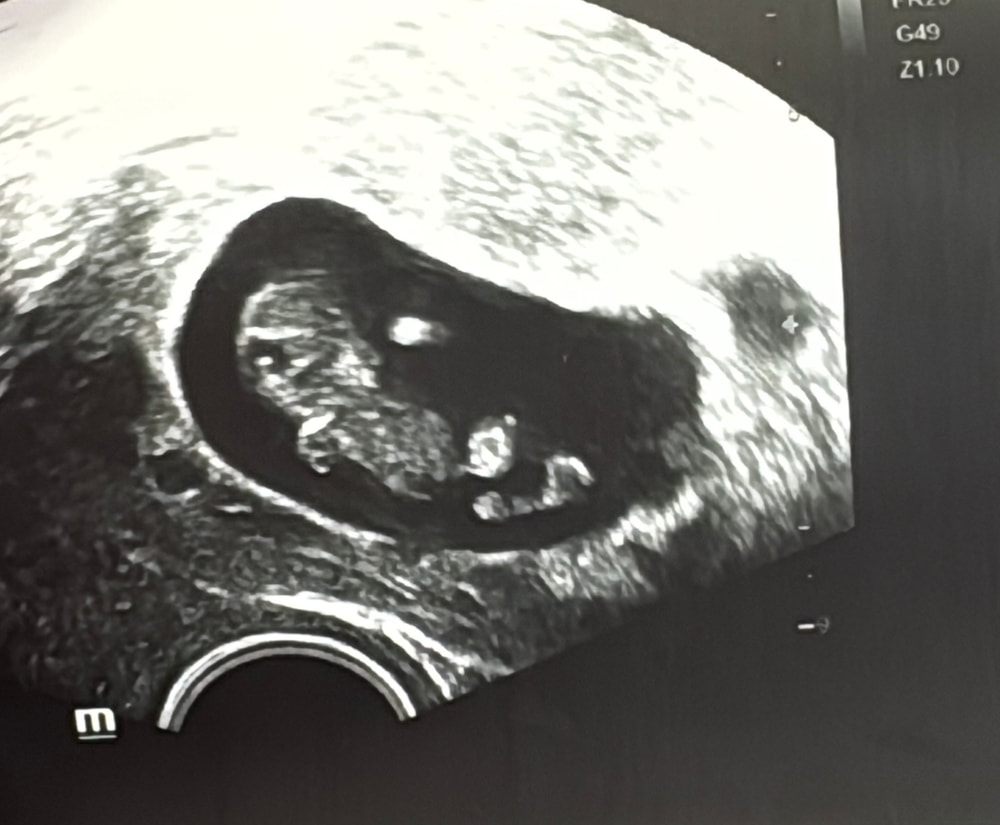

Моя тревожность гоняет меня еженедельно на УЗИ, как хорошо, что это не вредит малышику (а только моим финансам😂). Была у неизвестного мне врача. В итоге по КТР срок поставили меньше, чем по факту. Сердцебиение тоже 150 (было 170). По мнению врача все в порядке. По моему мнению, верните мне прежние замеры, они мне больше нравились 😂 скоро уже опять пройдет неделя с этого узи, рука так и порывается записаться куда-то в клинику.